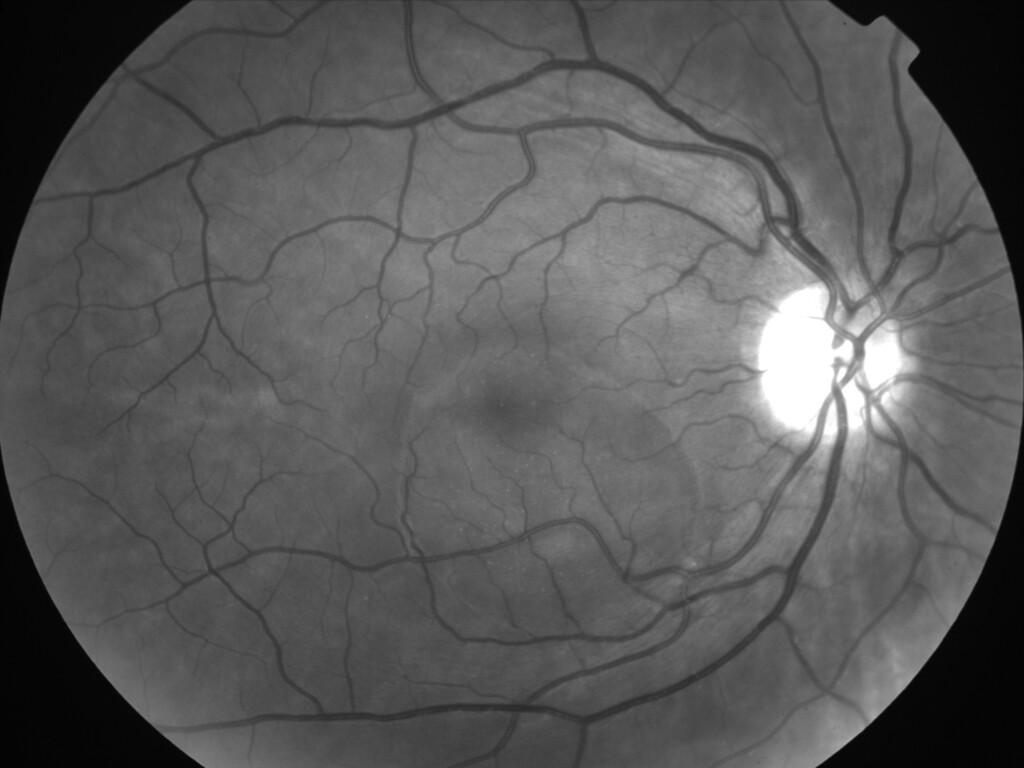

CHORIORETINOPATHIE SEREUSE CENTRALE

IM000006.jpg